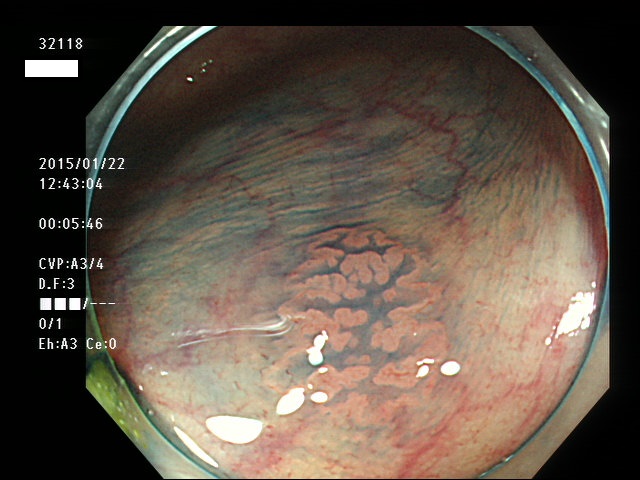

上記100名より抽出した平坦・陥凹型腺腫(=癌化の危険が高いが見落としやすい病変)の内視鏡写真

32101 32103 32105 32107 32108 32109 32110 32113 32114 32115 32116 32118 32119 32121 32123 32126 32129 32131 32132 32133 32134 32135 32138 32140 32141 32142 32143 32146 32147 32149 32150 32151 32152 32153 32154 32155 32156 32159 32160 32161 32163 32164 32167 32168 32173 32175 32176 32178 32183 32185 32187 32189 32190 32191 32194 32195 ・・・・の56名